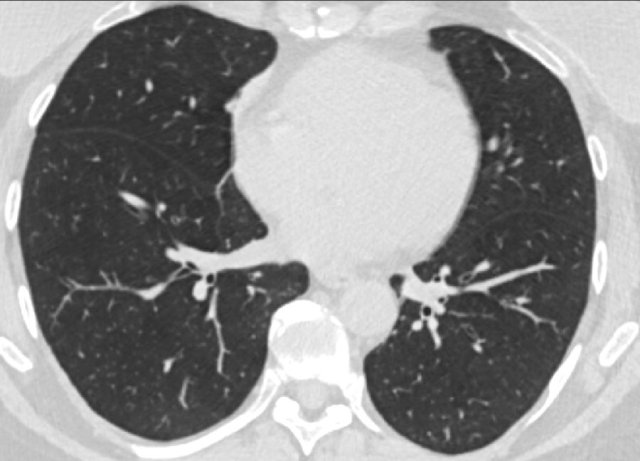

CO-RADS 1. Normal chest CT. CO-RADS 1. Normal chest CT.

CORADS 1

COVID-19 is highly unlikely.

The CT is normal or there are findings that indicate a non-infectious disease like congestive heart failure, sarcoid, histoplasmosis, malignancy, UIP or fibrotic NSIP (if unchanged to prior examination).

An exeption has to be made for the first few days of a mild infection when the CT can be normal.

The CT-image is of a patient with complaints for five days.

There are no abnormalities and the PCR was negative.